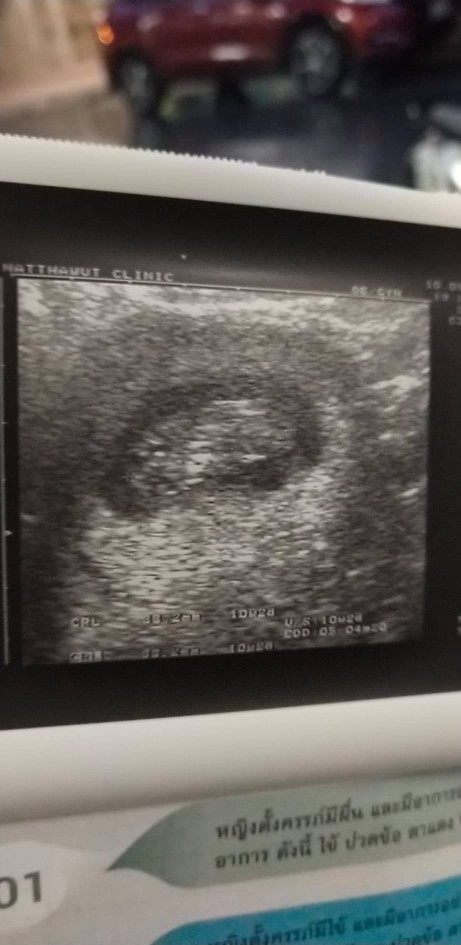

ซาวตอน9weekค่ะ